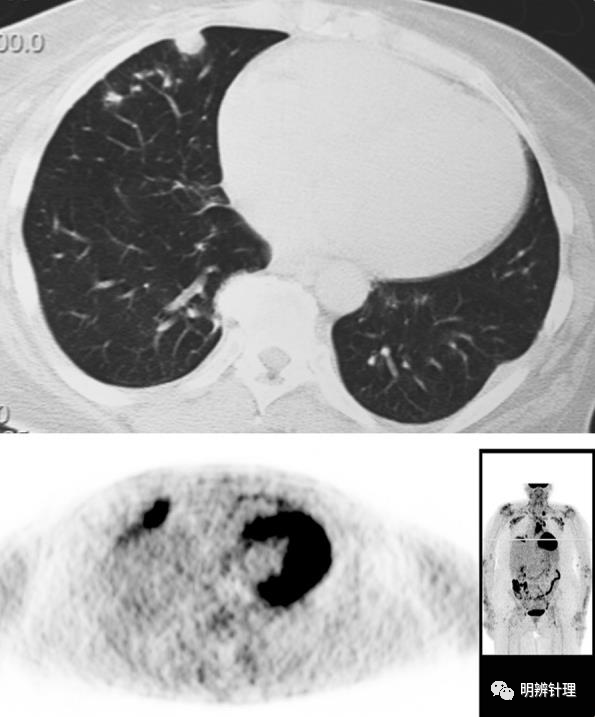

患者类风湿关节炎病史,右肺中叶胸膜下见实性结节灶,周边见多个小结节灶,小结节周围见磨玻璃渗出。

诊断结果:类风湿结节